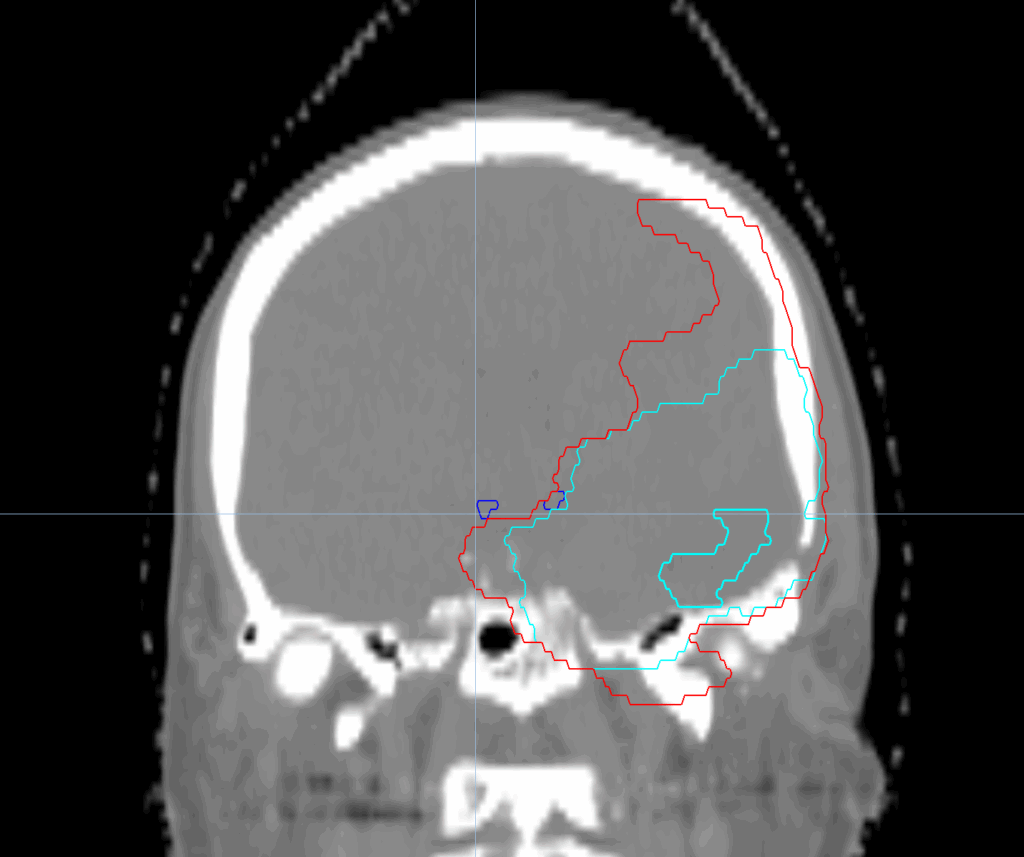

Planning CT Images

PTV(s) Volume, Length

280 cc, 12 cm